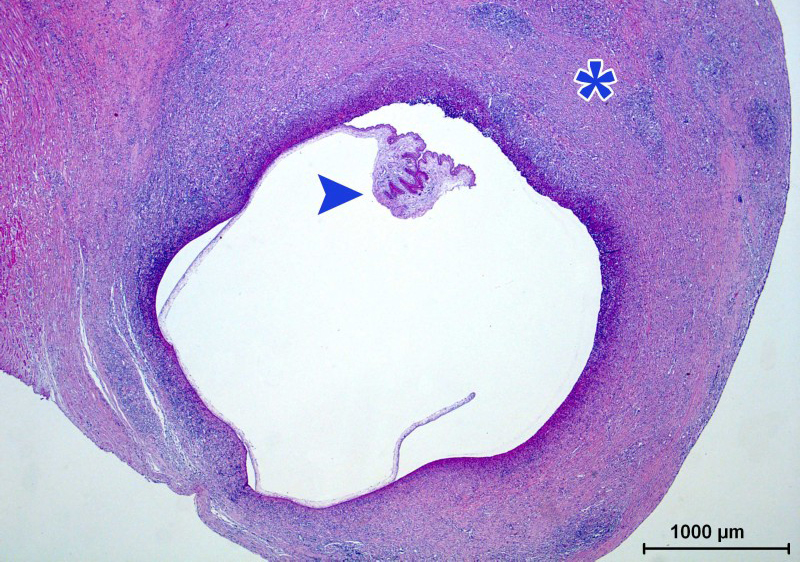

neurocysticercosis

脑囊虫病

术语缩写脑囊虫病(neurocysticercosis,ncc)同义词囊虫病定义由猪肉

囊虫病:一种常见的中枢神经系统寄生虫感染